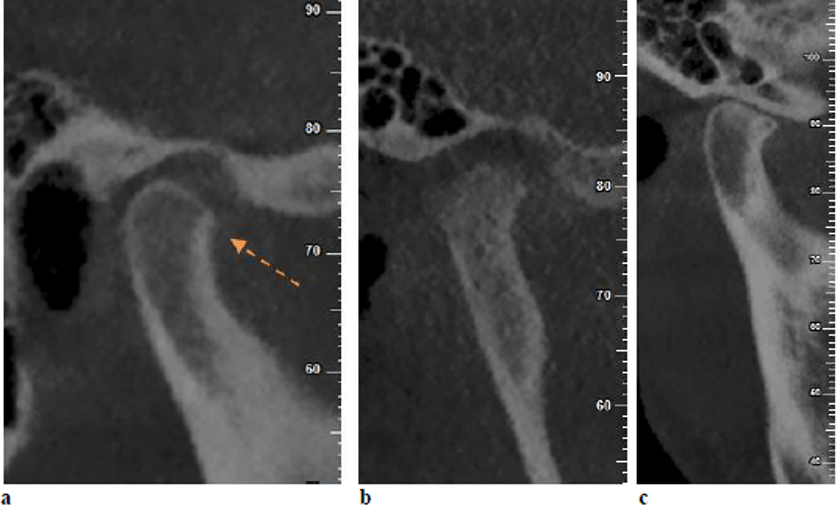

Cambios óseos en ATM evaluados con tomografía maxilofacial (cone beam)

Los trastornos de la articulación temporomandibular son un grupo de afecciones musculoesqueléticas que se consideran la principal causa del dolor orofacial no dental. Estos trastornos constituyen la segunda afección musculoesquelética más común después del dolor lumbar. Se ha informado de que su prevalencia varía entre el 16,3 % y el 68 % en la adolescencia...